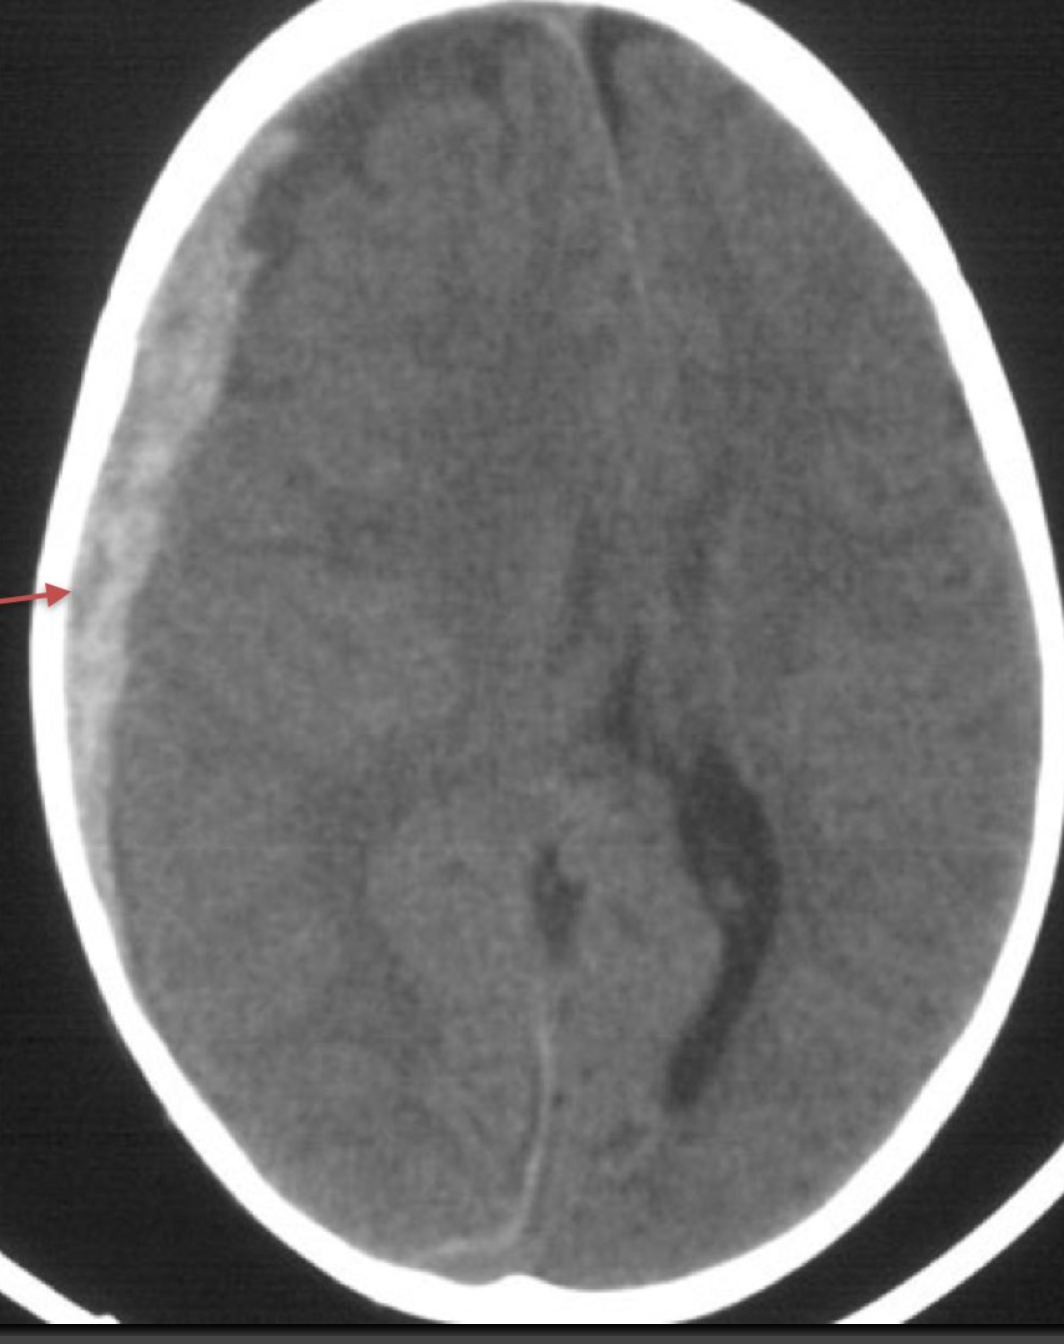

subdural haematoma